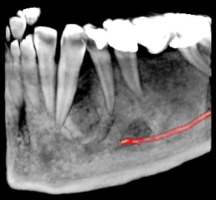

Зъбните снимки, независимо дали са секторни, панорамни зъбни снимки, телерентгенографии или друг вид се съхраняват на нашите сървъри неограничено дълго време.

Зъбните снимки са налични в няколко различни файлови формата - DICOM (DCM), PNG и JPG, което улеснява свалянето им на личните компютри.

Денталните медици могат с лекота да правят всички необходими обработки и измервания на дигиталните зъбни снимки, което улеснява подготовката за лечебния процес на пациента.